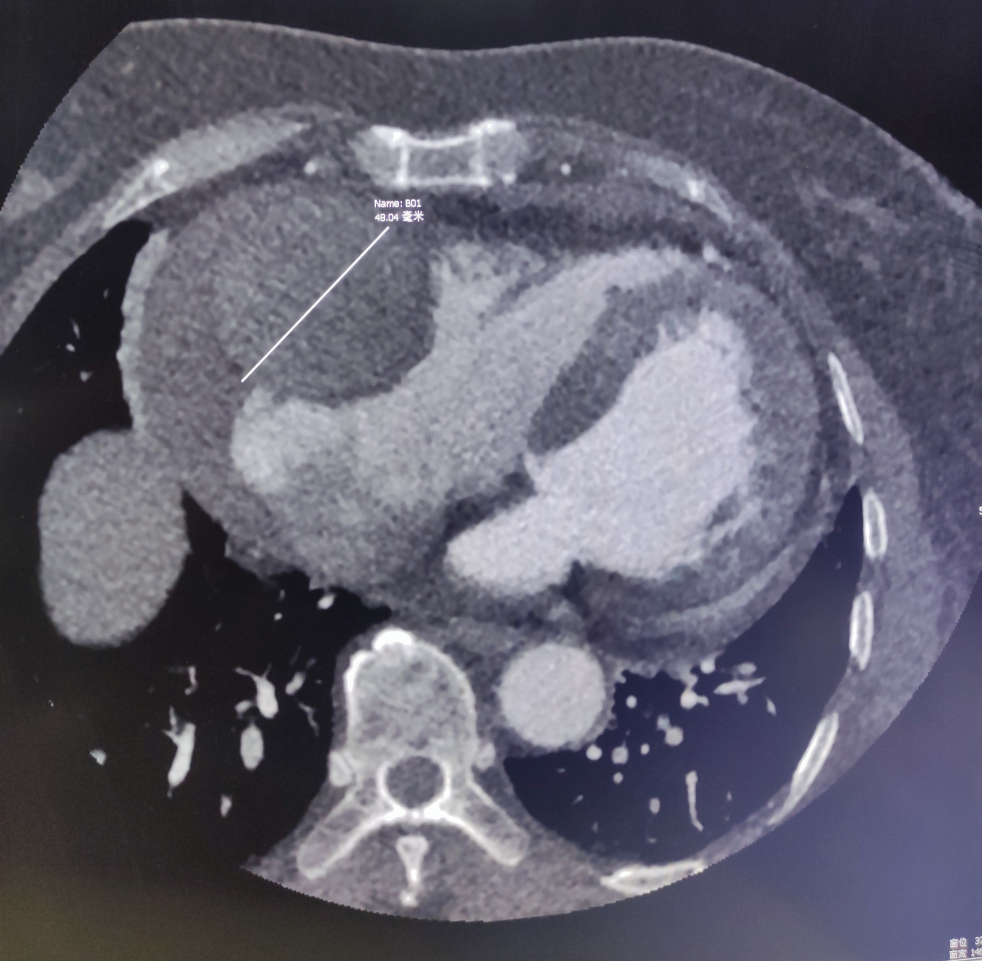

冠状动脉瘤的形成原因在于,各种因素影响下动脉中膜层弹力板断裂破坏,动脉内压力作用下管壁逐渐膨胀,形成瘤样扩张结构。

巨大动脉瘤原因排除冠脉粥样硬化。